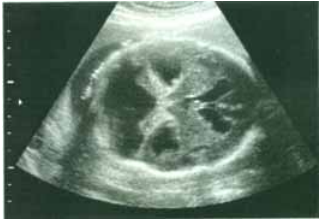

98 右圖超音波影像來自一名妊娠 28 週的胎兒,請依圖選出最可能之診斷?

(A) Anterior fossa cyst (B) Dandy-Walker malformation (C) Holoprosencephaly (D) Lemon sign